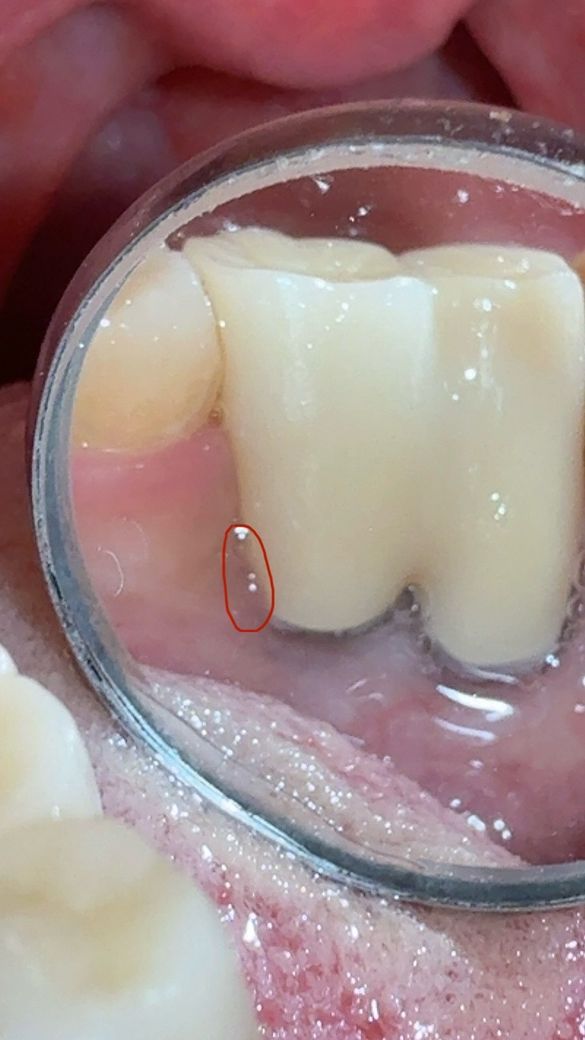

임플란트 보철물 주변의 잇몸에 관련하여 문의드립니다

임플란트 후 관리차원에서 치간칫솔과 워터픽을 사용하고 있긴합니다만 그래서 그런건지 주위염이 발생한건지 첨부된 사진에 체크한곳이

평소랑은 다르게 보철물 위로 잇몸살이 덮힌건지 부은건지 뭔가 보여서요

• 2번 째 사진

걱정할 정도의 염증 상태는 아닌 것 같습니다. 꼭 잇몸에 염증이 있지 않더라도 잇몸 상태는 몸 컨디션에 따라 일시적으로 붓기도 하고 그렇습니다.